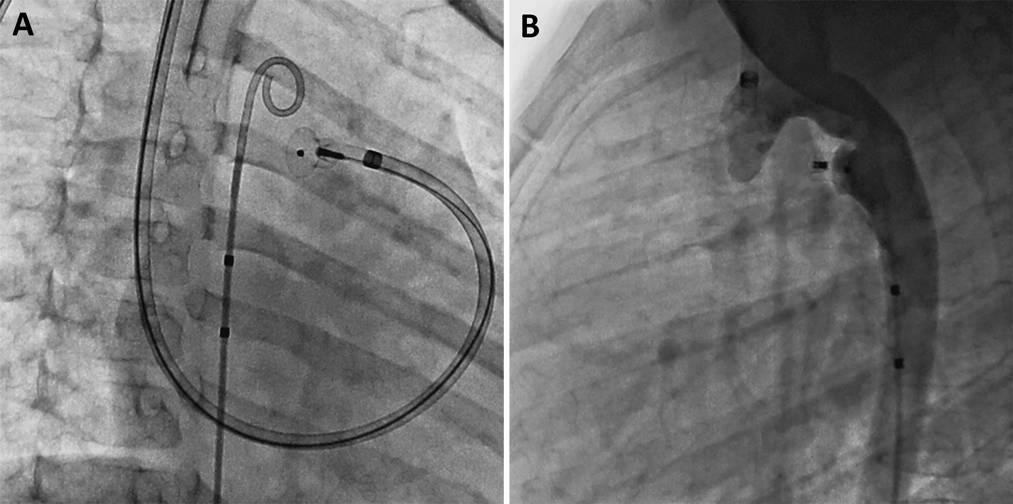

A 2 year-old (12 kg) female with an interrupted IVC with azygous continuation to the right superior vena cava was referred for transcatheter closure of a moderate PDA associated with left heart dilation. At catheterization, her pulmonary artery pressures were normal and her Qp/Qs was 1.7. Angiography confirmed IVC interruption and a moderate type A PDA (Fig. 1). The PDA was 7.5 mm long, the pulmonary artery end of the PDA measured 2 mm, and the aortic end measured 4.5 mm. The patient had a left aortic arch with normal branching. The PDA was crossed antegrade from the RIJ with the wedge catheter. An Amplatzer extra stiff wire (AGA Medical Corporation, Golden Valley, MN) was used to advance a 6 F 180 degree Amplatzer Torqvue delivery sheath (AGA Medical Corporation, Golden Valley, MN) across the PDA and into the descending aorta. A 5–4 mm Amplatzer Duct Occluder (ADO) (AGA Medical Corporation, Golden Valley, MN) device was chosen for closure. The delivery cable associated with this device is stiff; in the setting of a tortuous approach from the RIJ, we were concerned that this stiff cable may not reliably unscrew to facilitate device release. Thus, we took the floppier delivery cable from an Amplatzer Vascular Plug II (AVP II) (AGA Medical Corporation, Golden Valley, MN) device and attached it to the ADO device. Using the Amplatzer delivery sheath, the 5–4 mm ADO was deployed (Fig. 2A) and released without issue. Following device release, the aortogram showed no residual ductal flow and no aortic obstruction (Fig. 2B). The patient is doing well 6 months after the procedure with echocardiogram showing no residual PDA flow and no aortic or left pulmonary artery obstruction.

Fig. 2 (A) AP view of a 5-4 mm Amplatzer Duct Occluder device that has been deployed, but not released and delivered via an antegrade Amplatzer 180 degree delivery sheath from the right internal jugular vein. (B) Lateral aortogram following release of the Amplatzer Duct Occluder showing no residual flow through the duct and no aortic obstruction.